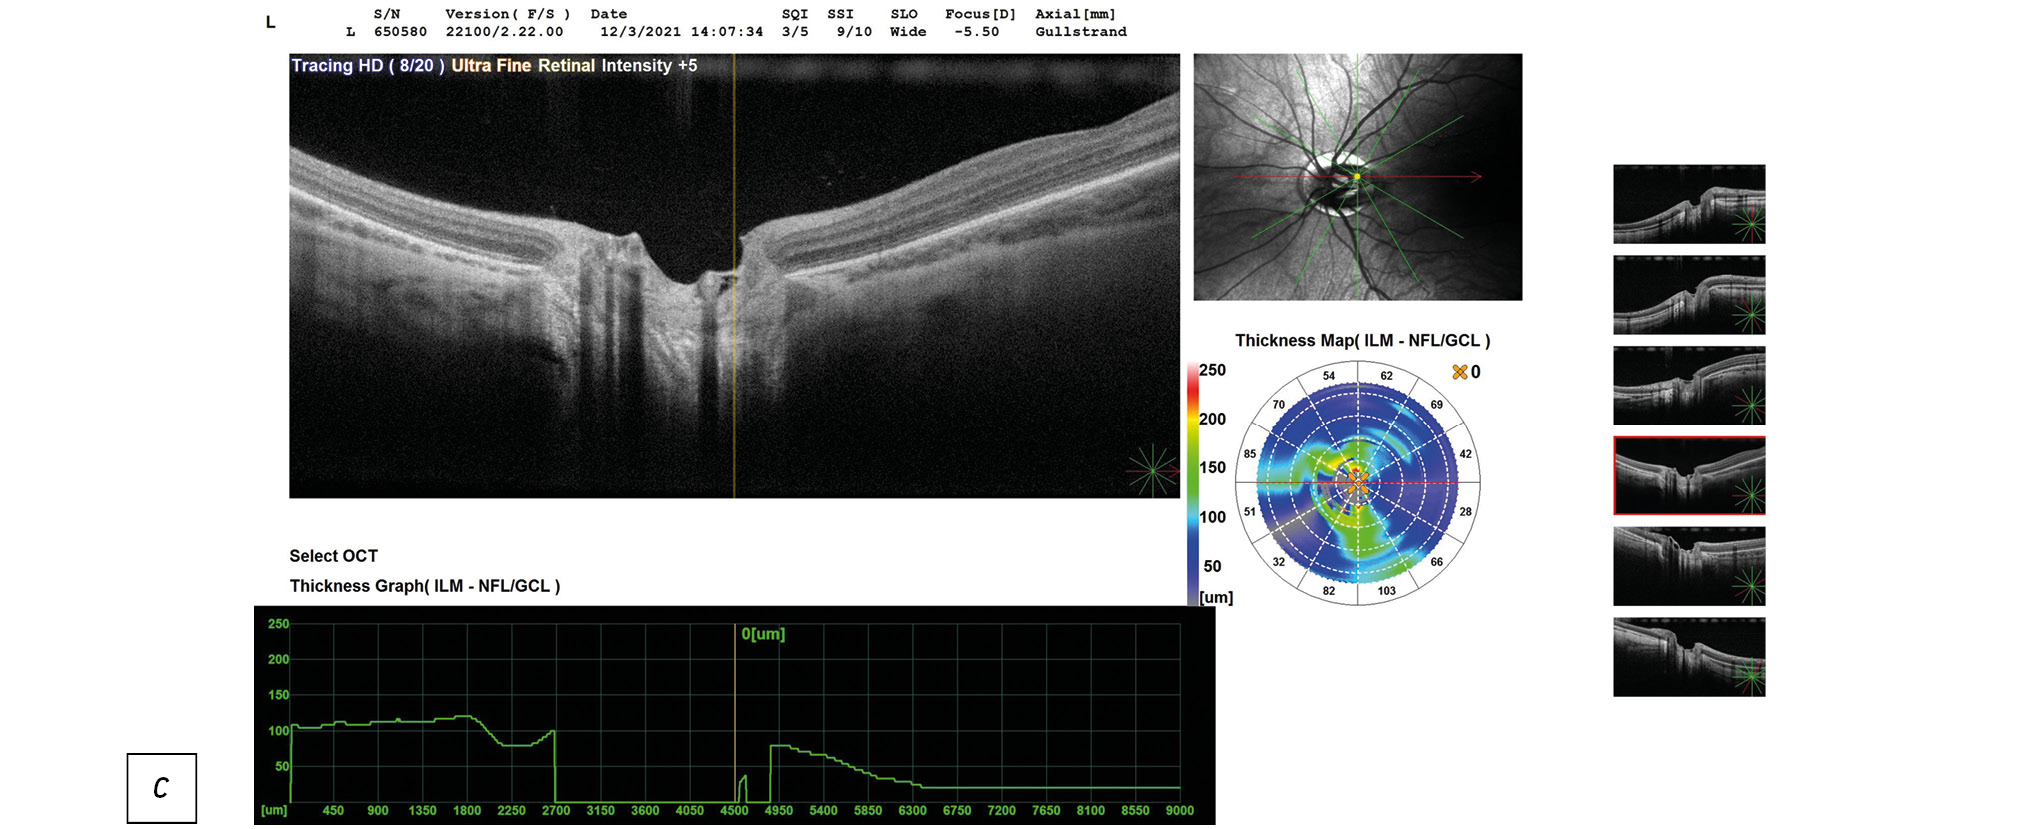

Данные ОКТ макулярной зоны сетчатки правого и левого глаз ребёнка представлены на рисунке 2. Данные ОКТ диска зрительного нерва (ДЗН) правого и левого глаз ребёнка представлены на рисунке 3.

Рис. 3, с. ОКТ диска зрительного нерва (ДЗН) левого глаза ребёнка: экскавация деформирована, расширена.

Справа — контур фовеолярной депрессии сглажен, отслойка нейроэпителия в макулярной зоне, деструкция и дезорганизация нейроэпителия и пигментного эпителия, центральная толщина сетчатки (ЦТС) 321 мкм, Слева — структура сетчатки в макуле не изменена, ЦТС 276 мкм. Справа экскавация ДЗН деформирована, расширена, заполнена субстратом однородной рефлективности средней степени, перипапиллярная щелевидная отслойка нейроэпителия в верхне-височном (рис. 3а) и нижне-височном (рис. 3б) квадрантах. Слева — экскавация ДЗН деформирована, расширена.